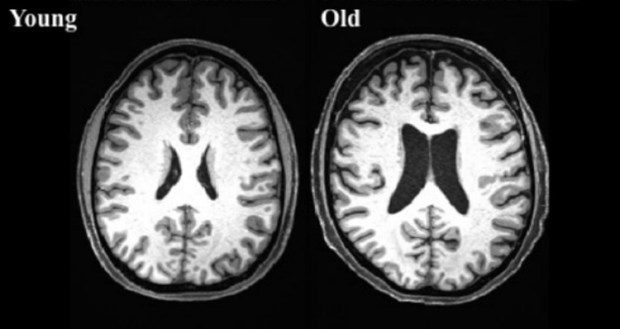

Brain scans from a 38-year-old, left, and a 73-year-old.